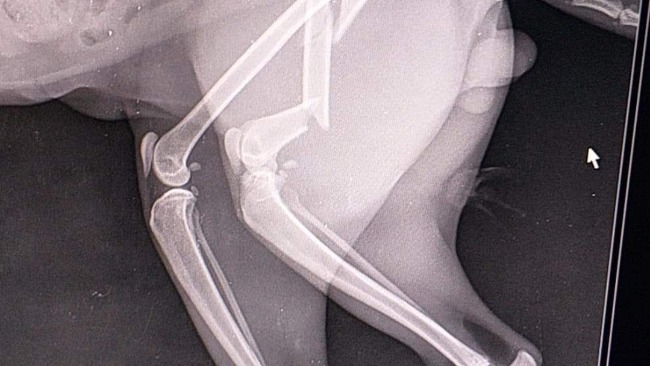

Witam wszystkich..Pisze ten post ponieważ mój kot,KAJTEK,członek naszej rodziny ucierpial dziś w wypadku.... złamał łapkę tylną,podczas wypadku,po wizycie na ostrym dyżurze dowiedziałam się że jest możliwość wstawienia implantu ale koszt przekracza moja możliwość finansową...ok 2,500,powiem wprost...zapisałam Kajtka na amputację😢 pnieważ, bez pomocy nie dam sobie rady ...zabieg w poniedziałek o 8.00.Kto kocha zwierzęta wiem że ten post chociaż na chwilę zostanie w pamięci...😞.